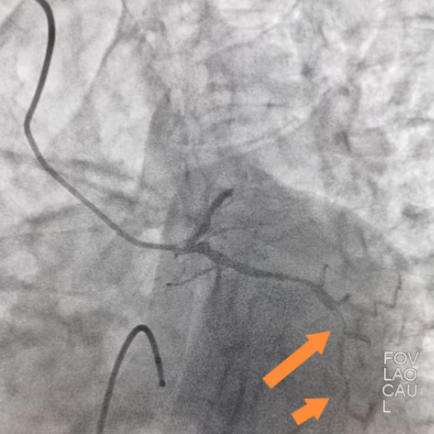

情况万分危急!瑞慈医院胸痛中心“绿色通道”立即启动。心血管内科崔勤主任团队火速会诊,结合心电图变化和症状,确诊老人是“急性下壁和右室心肌梗死,完全性房室传导阻滞”,当机立断:老人心跳这么慢,又有大面积心肌坏死,必须立刻做微创手术疏通堵塞的血管,这是救命唯一的办法!在快速征得家属同意后,崔勤主任团队制定了周密的方案:先给心脏装个临时的“起搏器”稳住心跳,接着立刻做心脏血管造影检查,如果需要就马上疏通血管。 △心血管内科崔勤主任(右一)团队术中 手术在导管室紧张进行,崔主任团队首先顺利在老人心脏里放置了一个临时“起搏器”,设定它每分钟发出60次电脉冲,代替坏掉的“电路系统”,暂时保住心跳。 刚放完临时起搏,患者再次出现心脏骤停,这次是室颤,患者瞬间意识丧失,团队成员迅速反应,立即启动心脏按压,电除颤,就在200J电流波迅速通过心脏,心律恢复。此时血压已然偏低,通过迅速的心脏血管造影,崔主任快速锁定病根——除了一根血管(左回旋支)也有多处严重狭窄外,另一根重要的血管(右冠状动脉)中间段完全堵死了!这根闭塞的血管就是导致心梗的“元凶”。 在临时起搏器的保护下,崔主任团队精准操作。用一根细如发丝的导丝小心翼翼地穿过了完全堵死的血管段,然后用小球囊把堵塞处撑开,最后精准放入一枚冠状动脉支架,血流完全恢复畅通! 崔勤主任提到,“这么大年纪的老人,心脏血管多处严重堵塞,加上心跳慢到随时会停,又突发心脏室颤,救活他就像走钢丝,风险极高。这次能成功,靠的是迅速判断,沉着应战,关键是稳定的技术发挥以及整个胸痛急救团队的完美配合。心脏血管堵住后,心肌细胞每分每秒都在死亡,我们必须跟时间赛跑,抢回生机!” 南通瑞慈医院心血管内科一直致力于提升对心脏急危重症的救治能力,通过建设规范的胸痛中心,不断优化抢救流程。这位高龄、高危、病情复杂老人的成功获救,正是医院强大综合实力的证明,也为南通及周边地区老百姓的心脏健康筑起了一道坚实的防线。